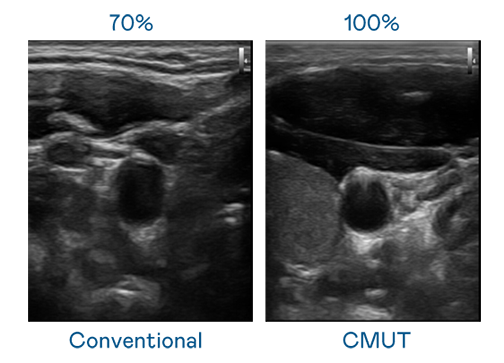

CMUT 技術是一種用電容式微機電元件來產生超音波訊號的技術。與傳統 PZT 壓電式技術相比,CMUT 頻寬增加 30%,更寬頻的超音波訊號讓影像解析度大幅提升,是實現高影像品質醫療超音波掃描、促進精準醫療發展的關鍵技術。

大頻寬帶來超清晰影像

超音波影像的解析度高低,首先取決於探頭能發出的訊號頻寬。麻花mv星空mv梦幻mv CMUT 可提供高清晰的超音波訊號,提供高頻寬、高靈敏度、影像紋理細節更高的超音波影像,協助醫護人員縮短影像判讀時間及利用精準的醫療影像進行診斷。